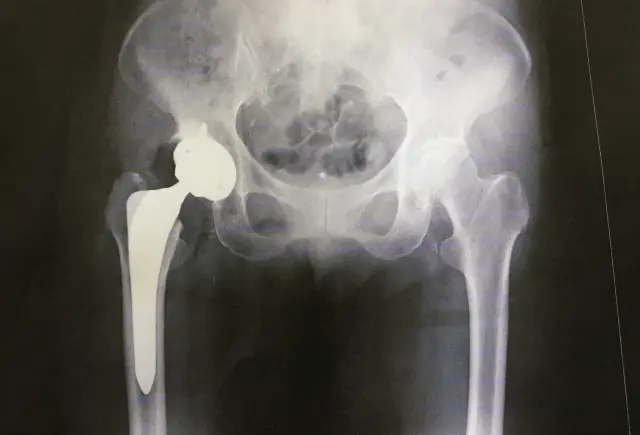

臼蓋形成不全という言葉、少し難しく聞こえますよね。簡単に説明すると、股関節の骨盤側にある「受け皿(臼蓋)」が生まれつき浅く、太ももの骨頭をしっかりと覆えていない状態のことです。本来なら屋根のように大腿骨頭を守るべき部分が浅いため、股関節全体が不安定になりやすく、関節に余分な負荷がかかり続けてしまいます。

日本整形外科学会の調査でも、成人女性の2〜7%がこの状態にあるとされています。男性に比べて女性に多く見られるのが特徴で、特に出産後や育児中に股関節の痛みとして気づく方が多いです。「なんとなく股関節が痛いな」という違和感から始まり、整形外科でX線を撮って初めてわかるケースも多く見られます。

臼蓋形成不全を放置してしまうと、10〜20年かけてゆっくりと関節軟骨がすり減り、変形性股関節症へと進行していきます。初期は「なんか違和感があるな」という程度でも、気づいたときには立ち上がりや歩行が痛くなっていた、という方は実際に多くいらっしゃいます。だからこそ、早い段階での対処がとても重要なんです。